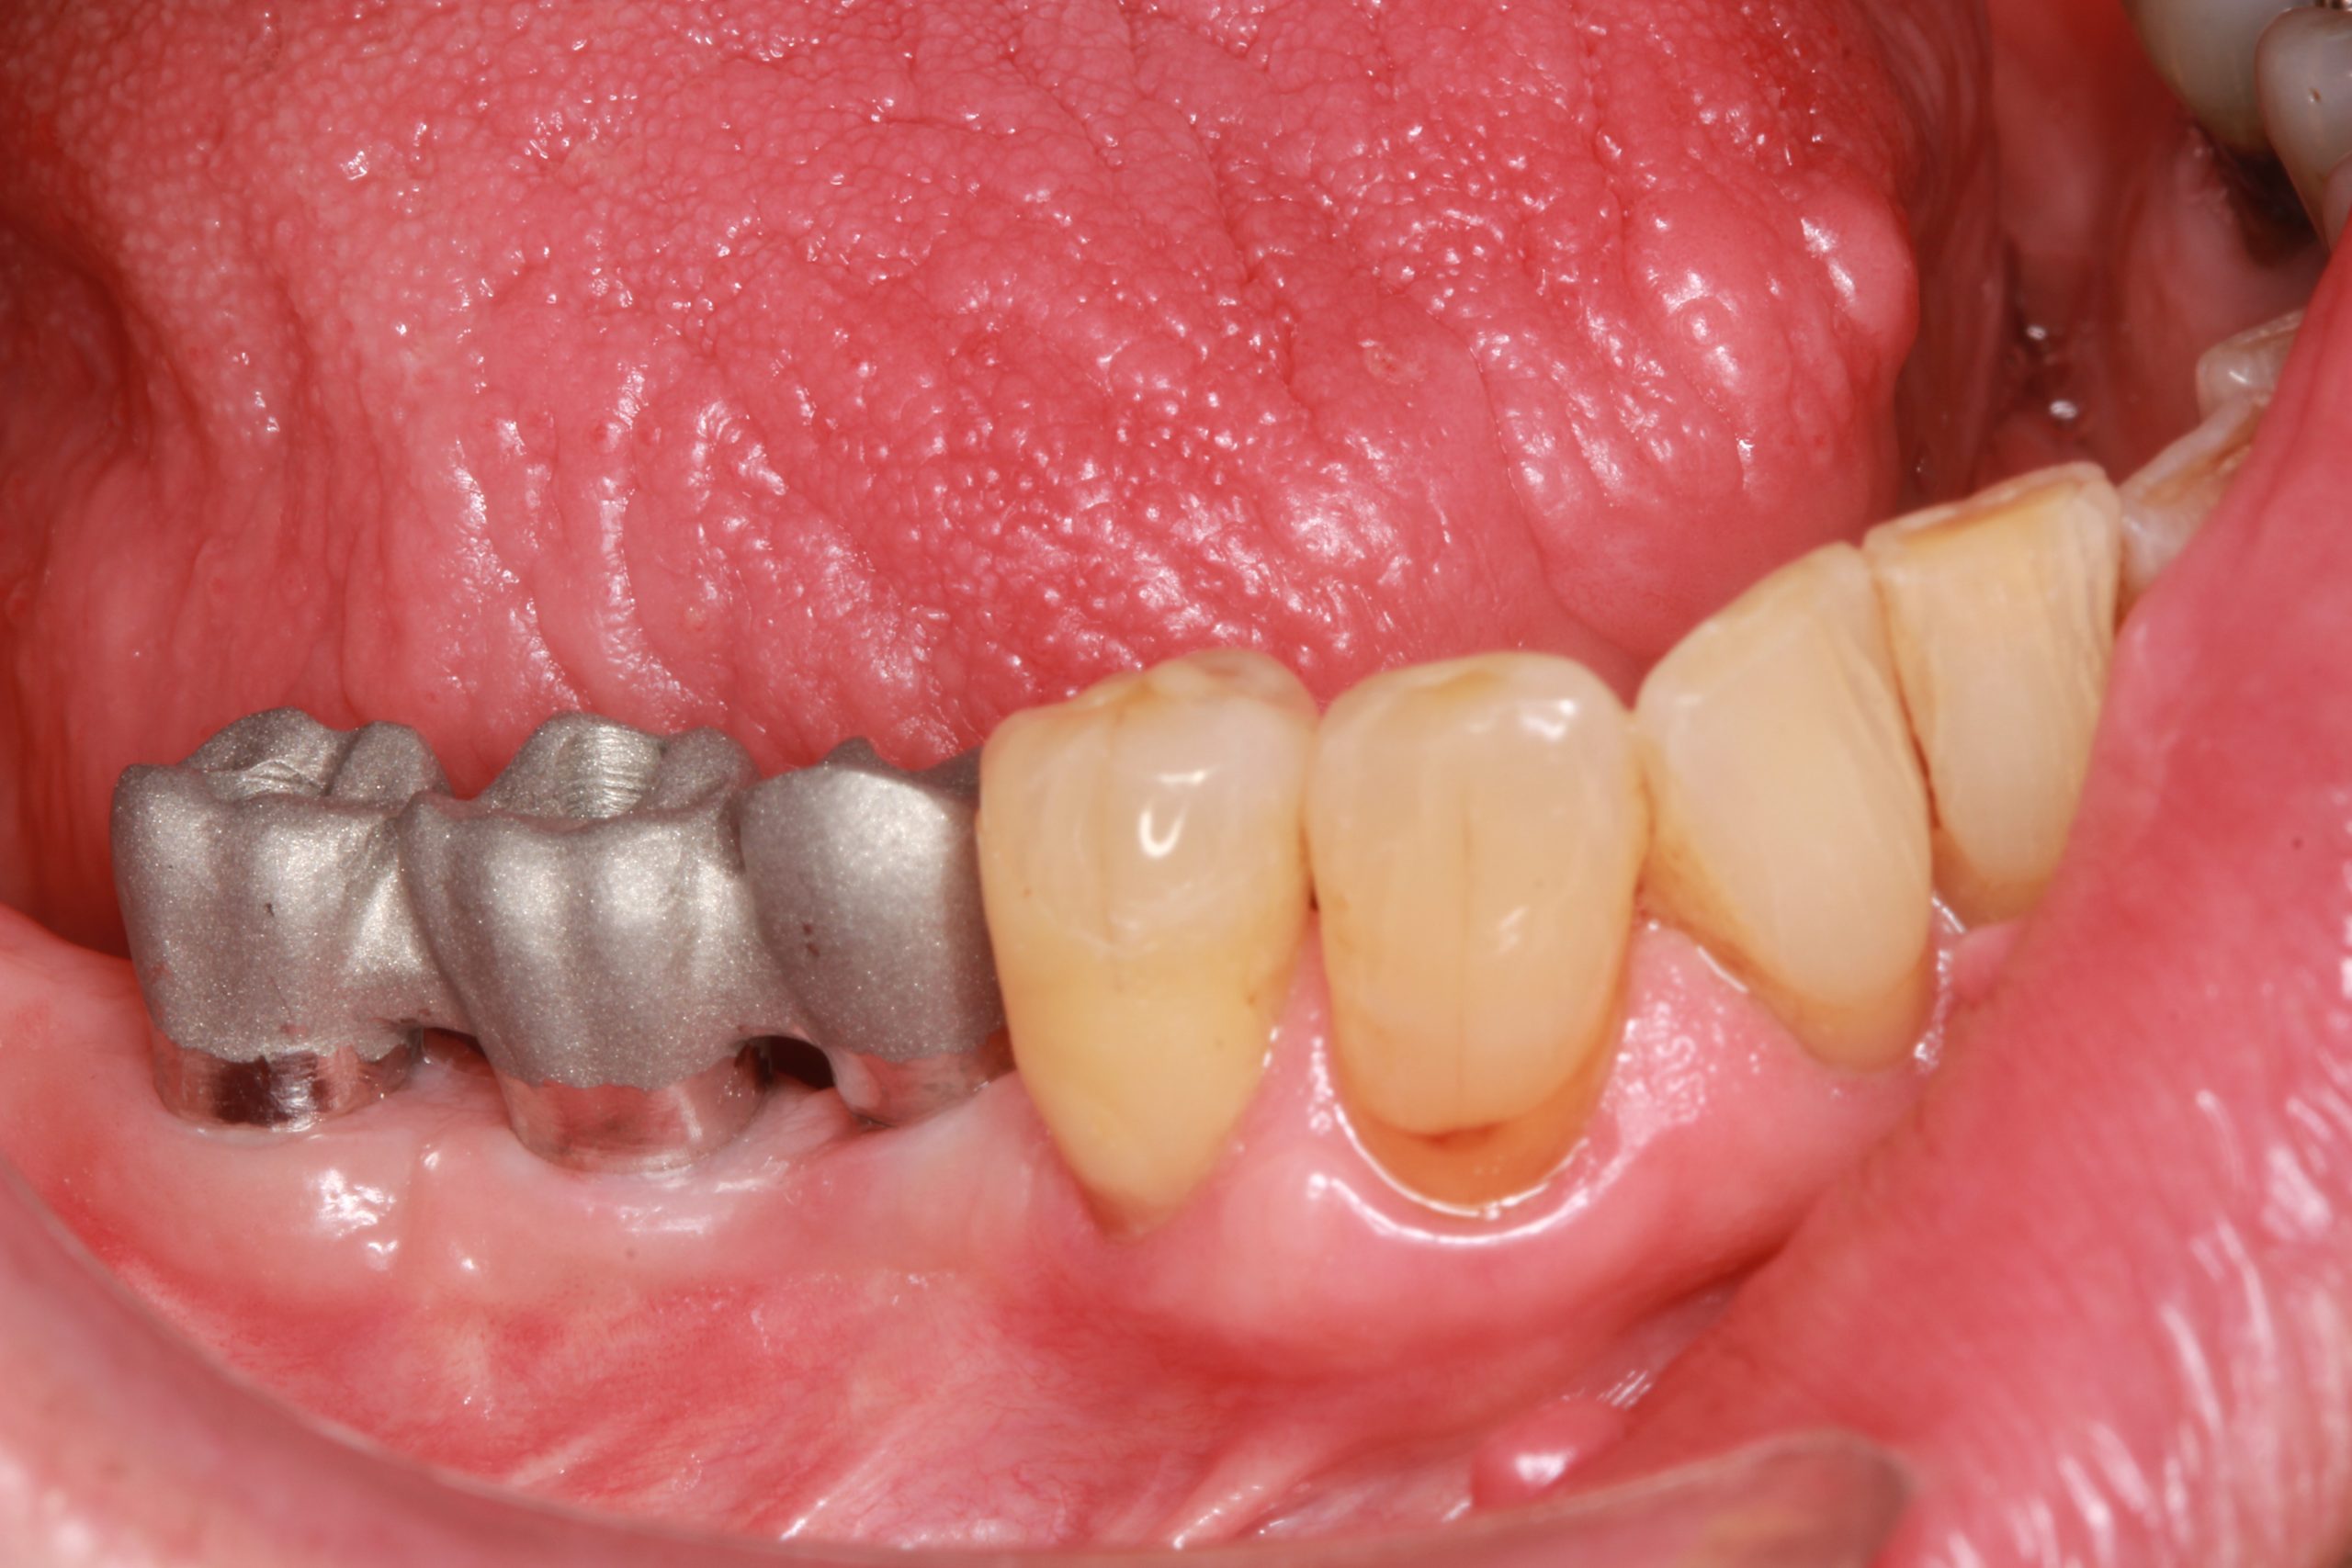

Eine festsitzende verschraubte metallkeramische Zahnbrücke wurde entworfen. Die Anprobe der Suprakonstruktion zeigt, dass sie richtig sitzt.

Der finale Zahnersatz wurde im Patientenmund verschraubt. Die Erwartungen des Patienten auf ein funktionelles und ästhetisches Ergebnis, das langfristig stabil und nachhaltig ist, wurden erfüllt.